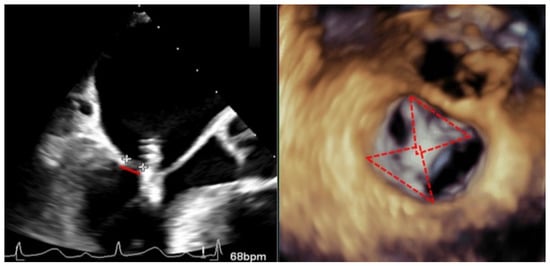

The echocardiographic criteria to diagnose SLDA are the color Doppler demonstration of significant MR through the leaflet interface, new excessive leaflet mobility following device deployment, and a lack of diastolic tissue bridge by 3DTEE; acute changes in pressure also occur with the new appearance of the v-wave after the initial improvement after clip implantation (Figure 5). Once the complication has occurred, the TEE undoubtedly helps in determining the mechanism of the loosening of the leaflet by measuring the portion of the free leaflet with respect to the measurement prior to implantation [13]. Other mechanisms, such as tear or perforation, can be viewed as a disruption of leaflet integrity reaching the leaflet edge or not, respectively. An excessive clip–leaflet tension can be shown as a shape distortion affecting leaflet coaptation, without disruption of the leaflet integrity. The entrapment of the clip in leaflets or subvalvular structures with chordal rupture appears in TEE as new excessive leaflet mobility [1]. Chordal entanglement should be avoided by minimizing device manipulation below the mitral valve and not advancing the system deep into the left ventricle.

Figure 5.

Two-dimensional transesophageal echocardiogram showing a very severe mitral regurgitation after the partial detachment of a clip and a leaflet tear prolapsing in the left atrium (yellow arrow). Three-dimensional transesophageal echocardiogram in the enface mitral view, where a clip can be seen attached to the anterior leaflet (red arrow) and loose from the posterior with a lack of diastolic tissue bridge. In the lower panel, simultaneous recording of left atrium (green), pulmonary artery (yellow), and aortic pressure (purple): baseline, post clip implantation and after detachment.